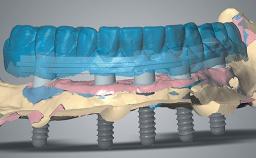

His main interests are in Computer Aided Maxillofacial and Implant Surgery, with a focus on Interdisciplinary Treatment, and in Orthognathic Surgery. He has many publications and lectures worldwide on digital tools, bone grafts, implants in the treatment of the esthetic area, complications, and the treatment of fully edentulous patients.